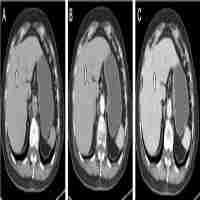

| Abstract | Florid lymphoid hyperplasia in the terminal ileum can present to surgeons as an acute abdominal pain. Only few cases were reported in the literature. Our case illustrates that a rare case of florid lymphoid hyperplasia can present to surgeons as acute appendicitis. During the operation the gross appearance may mimic Crohn's disease. A limited resection is sufficient to clinch the diagnosis of florid lymphoid hyperplasia / Crohn's disease. In florid lymphoid hyperplasia limited resection may be curative. |